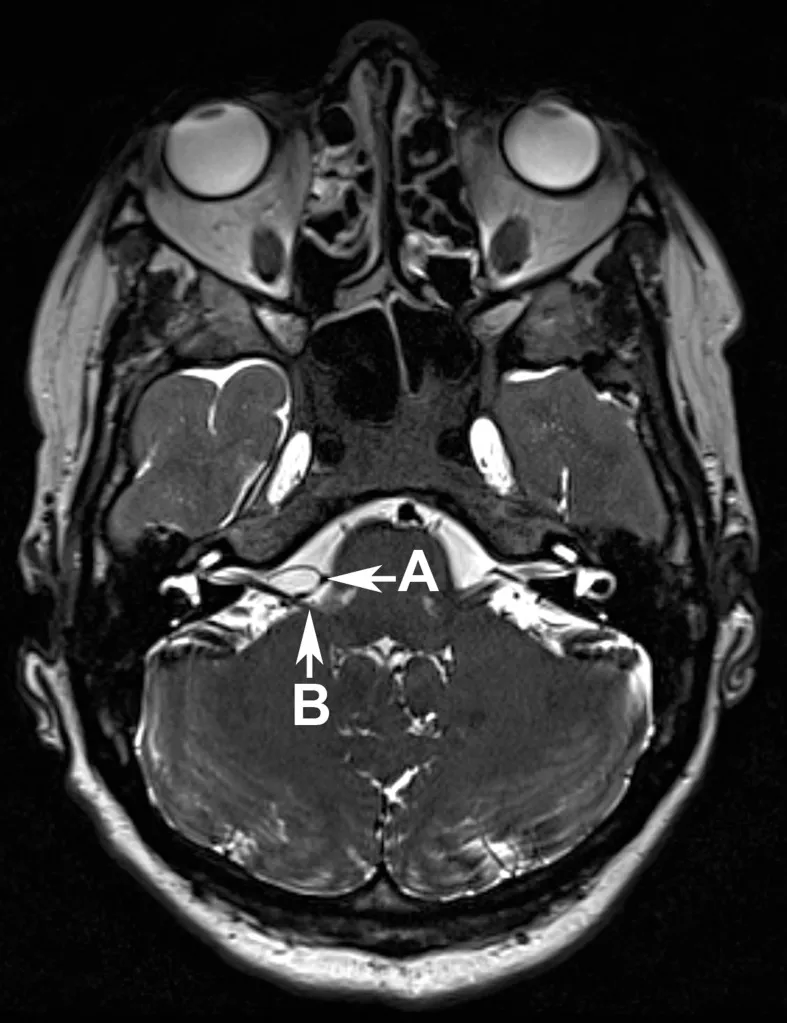

这张脑部核磁非常清晰显示了小脑后下动脉(箭头A),它压迫了面神经(箭头B),就在面神经从脑干出来的地方。

MRI发现小脑前下动脉与椎动脉明确压迫出脑干区的面神经(图1)。